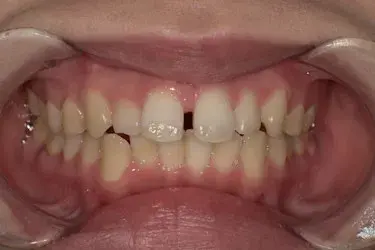

治療期間 約3カ月

プラン アーリープラン(8枚コース)

治療費 33万円(税込)